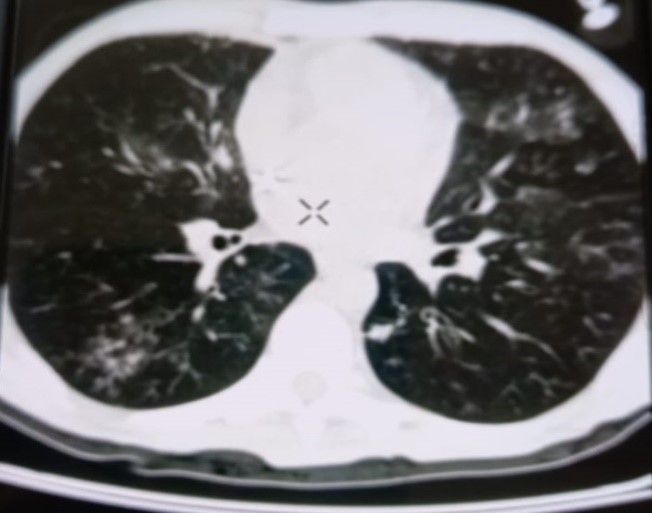

При проведении рентгенологического исследования органов дыхания в динамике спустя 2 недели с момента начала терапии данные компьютерной томографии высокого разрешения указали на следующие изменения: на фоне очаговой диссеминации в легких значительно увеличились по площади участки "матового стекла" в верхних долях обоих легких (описанные зоны неоднородные, сливные); площадь поражения легочной ткани - около 35-40%. В средних и нижних отделах легких с двух сторон выявлялись многочисленные перибронхиальные очаги до 3 мм в диаметре по типу «дерево в почках». В S 6 справа определялась зона альвеолярной инфильтрации. Выпот в плевральных полостях не определялся; внутригрудные лимфоузлы не увеличены. Заключение: признаки двусторонних полисегментарных интерстициально-инфильтративных, диссеминированных мелкоочаговых изменений легких, средняя вероятность вирусной пневмонии (в том числе COVID-19), в сочетании с диссеминированным процессом в легких (рис. 1-4).

Рисунок 1

Рисунок 2

Рисунок 3

Рисунок 4

Рис. 1-4. Компьютерная томограмма пациента Т., с ВИЧ: чередование участков «матового стекла» с диссеминированным процессом, инфильтрацией легочной ткани справа, наличие симптома «дерево в почках» (респираторный бронхиолит).

Учитывая на подозрительные в отношении туберкулеза легких КТ-признаки, пациенту впервые проведена метод ПЦР-диагностики выявления ДНК микобактерий туберкулеза, который показал положительный результат, что позволило установить диагноз «Диссеминированный туберкулез легких, двусторонний. КУМ «-» в сочетании с коронавирусной инфекцией COVID-19 средней степени тяжести, пневмоцистной пневмонией и бактериальной пневмонией» у пациента с ВИЧ-инфекцией 4В стадии. Для дальнейшей терапии пациент был переведен в стационар туберкулезного профиля.